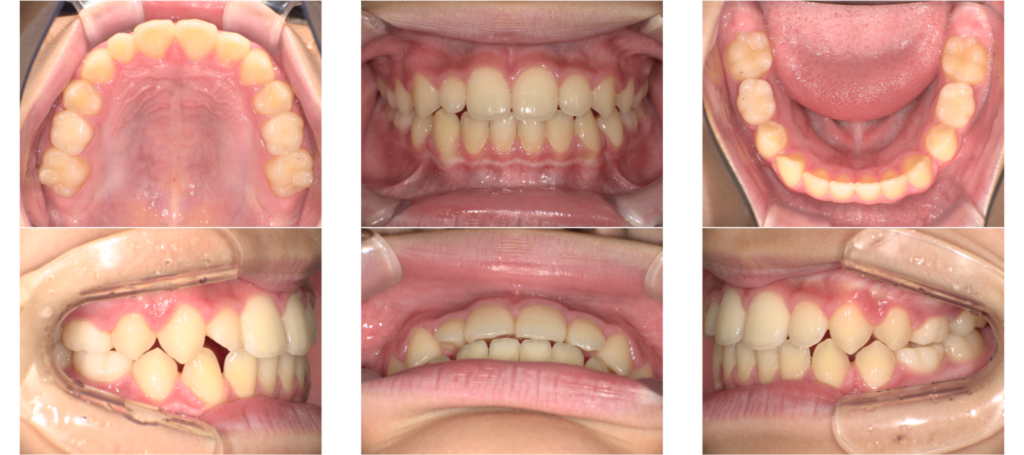

治療前 / 現在

治療開始時

現在

BWS撤去後の変化

BWSを外した後は一時的に前歯に隙間が出たり少し出っ歯になることがあります。

しかしなんの問題もありません。

しっかりとアクティビティとマウスピースの装着を続ければ

数ヶ月かけてゆっくりと上顎の骨ができてより綺麗になっていきます。

後半のアクティビティ

この頃にはアクティビティの後半に差し掛かっていました。

この頃は飲み込み方、頬と唇のアクティビティを行なっていましたが

いつも通り頑張ってくれて順調に進みました。

アクティビティは終了し経過観察をしていますが歯並びも安定しています。